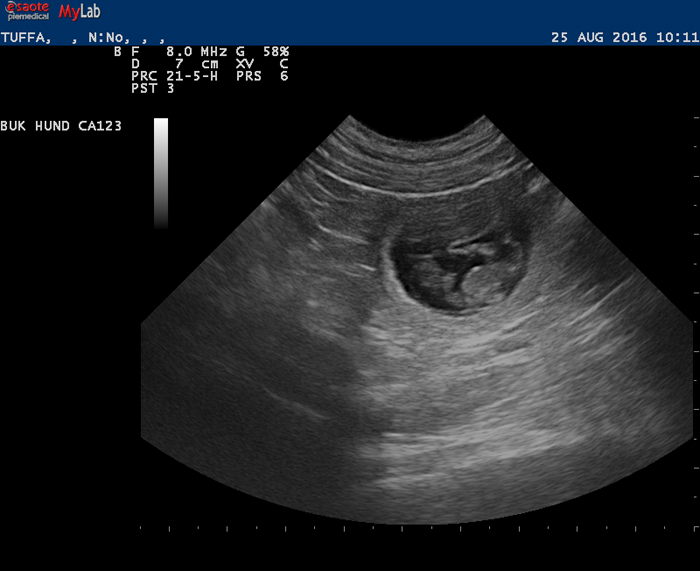

Ultraljud på måndag

På måndag gör vi ultraljud för att se om Fanny har valpar i magen. Håll tummarna!